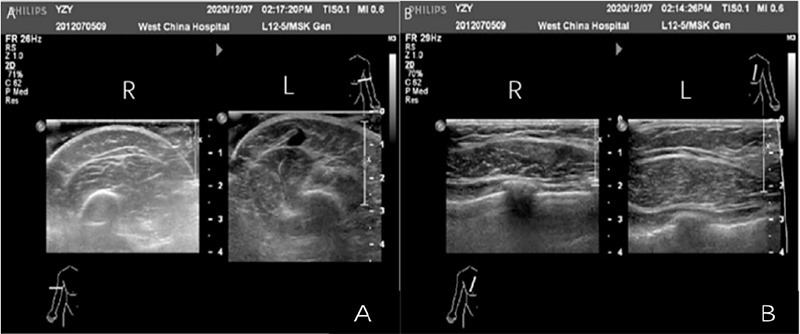

Klippel-Trenaunay综合征是一种罕见的先天性疾病,其特征是三种症状:毛细血管畸形、静脉异常、骨骼和软组织肥大。该综合征通常表现为葡萄酒色斑,静脉曲张和肢体肥大,可导致严重的并发症,如静脉血栓栓塞和出血。我们报告一例13岁的女性,出生后左上肢和肩部出现红斑。采用了一种有效的治疗方法,其中包括一个多学科的专家团队,专门从事皮肤病学和血管外科的各个领域,所有人都以患者的健康为核心进行合作。这种方法强调基于患者偏好的个性化策略。

Klippel-Trenaunay Syndrome is a rare congenital disorder characterized by a triad of symptoms-capillary malformations, venous abnormalities, and hypertrophy of bones and soft tissues. The syndrome often presents with port wine stains, varicose veins, and limb hypertrophy, which can lead to significant complications such as venous thromboembolism and bleeding. We present a case of a 13 ' year female, with erythema in left upper limb and shoulder since birth.. An effective treatment method was employed, which incorporated a multidisciplinary team of experts specialized in various fields of dermatology and vascular surgery, all working collaboratively with the patient's well-being at the core of their efforts. This approach emphasized a personalized strategy based on the patient's preferences.